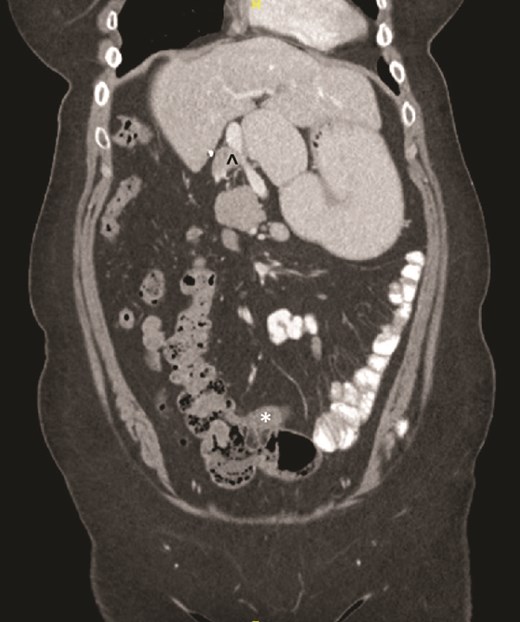

On examination, the abdomen was soft but mildly distended. Bowel sounds were heard, and the epigastrium was mildly tender. Standard bloodwork was normal. Review of an abdominal computerized tomography (CT) scan from 4 years prior showed congenital malrotation of the bowel, with the small bowel to the left of the midline and colon entirely to the right (Fig. 1). There was partial agenesis of the dorsal pancreas (Fig. 2), azygous continuation of the inferior vena cava (IVC), a retroaortic and retrocrural left renal vein, and an unremarkable spleen alongside some splenules. The PV traversed anterior to the first part of the duodenum (Fig. 3). There was relative narrowing of the distal stomach and the duodenum was nondilated.

Preduodenal PV seen crossing the duodenum (D) causing partial obstruction.

A PDPV needs special consideration during duodenal and biliary tract surgery as there is an increased risk for ligation, tearing, division, and thrombosis due to excessive handling [1]. This is especially important during emergent laparotomy where cross-sectional imaging may not be performed prior to surgery. In our case, a CT scan was beneficial as the PDPV was readily visible traversing anterior to the duodenum and identifiable as a potential cause of duodenal obstruction. This was further confirmed during EGD when there was difficulty passing the gastroscope into the first part of the duodenum. This approach is similar to previous case reports where CT imaging and an EGD were performed prior to surgery [11, 12].